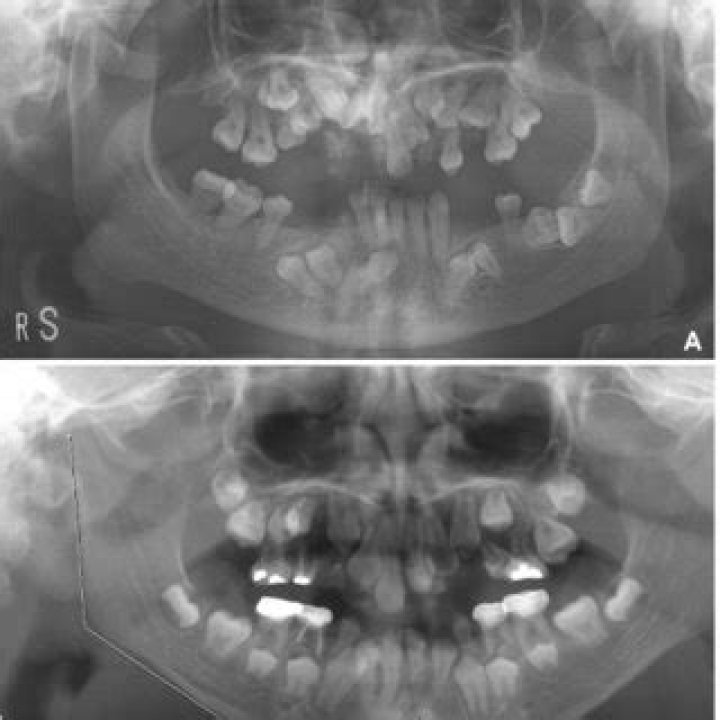

Missing or peg-shaped teeth are a common feature of actor cleidocranial dysplasia. Peg-shaped teeth are small, cone-shaped teeth that are often widely spaced. Missing or peg-shaped teeth can make it difficult to eat, speak, and smile. People with actor cleidocranial dysplasia may also have other dental problems, such as cavities, gum disease, and malocclusion (bad bite).

The dental problems associated with actor cleidocranial dysplasia can have a significant impact on a person's quality of life. Missing or peg-shaped teeth can make it difficult to eat and speak, and they can also lead to social problems. Cavities and gum disease can be painful and can lead to tooth loss. Malocclusion can make it difficult to bite and chew food, and it can also lead to jaw pain and headaches.

Understanding the connection between the dental features of actor cleidocranial dysplasia and the underlying genetic cause of the condition is important for several reasons. First, it can help to identify people who are at risk for developing the condition. Second, it can help to develop new treatments for actor cleidocranial dysplasia. Third, it can help to provide support and information to people with actor cleidocranial dysplasia and their families.